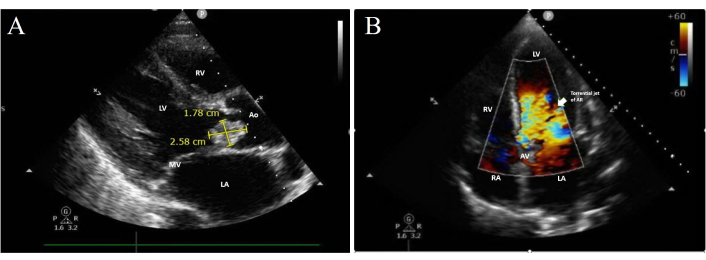

Transthoracic echocardiography (TTE) revealed a severely dilated left ventricle (LV) with mildly reduced systolic function, alongside a normal right ventricle (RV). A large vegetation measuring 2.58 cm × 1.78 cm was visualised on the flail left coronary cusp of the aortic valve (AV) (Figure 3A), resulting in torrential aortic regurgitation (AR) (Figure 3B).

Trans-thoracic echocardiogram. (A) Parasternal view showing a large vegetation on the left coronary cusp. (B) Apical 5-chamber view showing torrential AR. LA: left atrium; MV: mitral valve; LV: left ventricle; RV: right ventricle; Ao: aorta; RA: right atrium; AV: aortic valve; AR: aortic regurgitation.